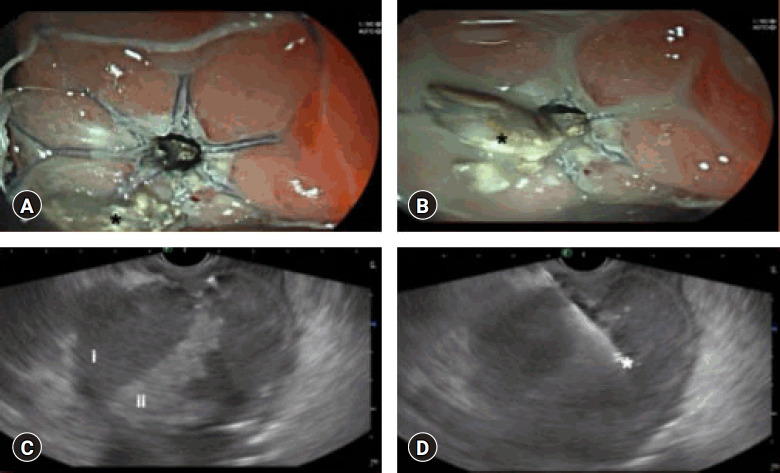

背景/目的:壁状坏死(WON)是儿童急性胰腺炎的严重并发症,其内镜治疗证据有限。本研究评估了超声内镜(EUS)引导下放置腔内金属支架(LAMS)治疗小儿WON患者的疗效和安全性。方法:这项开放标签前瞻性研究纳入了5-18岁继发于急性坏死性胰腺炎的儿童患者,这些患者于2021年1月至2023年7月在三级中心接受eus引导的LAMS治疗。临床成功,定义为12周时症状缓解和WON清除,是主要结局。次要结局包括技术成功、并发症和是否需要额外干预。结果:纳入11例患者,平均年龄15.5±3.1岁。12周内临床成功率90.9%,技术成功率100%。两名患者经历了支架闭塞,并用盐水冲洗处理;1例需要电视辅助腹膜后清创。平均住院时间5.4±3.3天。无重大不良事件报告。结论:eus引导下的LAMS放置是一种安全有效的替代手术治疗小儿WON的方法,具有较高的临床和技术成功率和最小的并发症。需要进一步的多中心研究来验证这些发现。

Background: Walled-off necrosis (WON) is a severe complication of acute pancreatitis in children, with limited evidence on its endoscopic management. This study evaluated the efficacy and safety of endoscopic ultrasonography (EUS)-guided lumen-apposing metal stent (LAMS) placement for WON in pediatric patients.

Methods: This open-label prospective study included pediatric patients aged 5-18 years with WON secondary to acute necrotizing pancreatitis that was managed with EUS-guided LAMS at a tertiary center from January 2021 to July 2023. Clinical success, defined as symptom resolution and WON clearance at 12 weeks, was the primary outcome. Secondary outcomes included technical success, complications, and the need for additional interventions.

Results: Eleven patients (mean age, 15.5±3.1 years) were included. Clinical success was achieved in 90.9% of the patients within 12 weeks, with a 100% technical success rate. Two patients experienced stent occlusions that were managed with saline irrigation; one case required video-assisted retroperitoneal debridement. The mean hospital stay was 5.4±3.3 days. No major adverse events were reported.

Conclusions: EUS-guided LAMS placement is a safe and effective alternative to surgery for pediatric WON, with high clinical and technical success rates and minimal complications. Further multicenter studies are required to validate these findings.